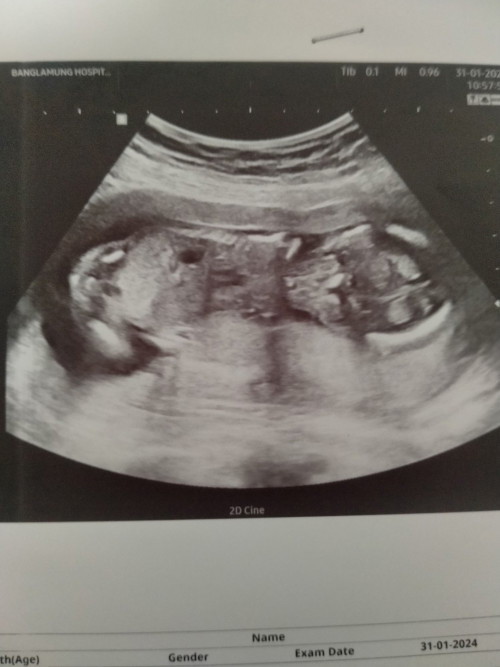

ภาพแรกของลูกสาวน้องอันอัน ตอนนี้หนู 33W ใกล้เจอหน้ากันแล้วค่ะกำหนดคลอด 14 กรกฎาคม นี้แล้วค่ะ